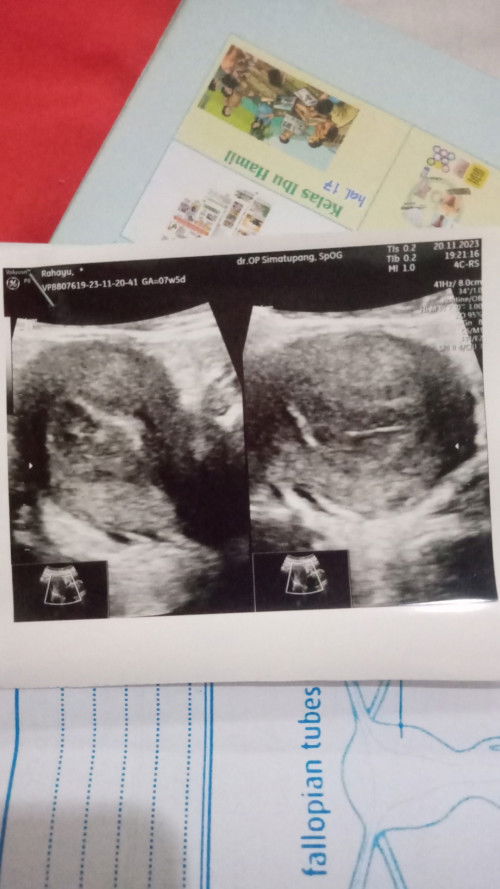

aku juga waktu itu hpht 4sept, aku ke dokter USG 14okt perhitungan perkiraan aku kandungan udh 6minggu, taunya pas USG kata dokter nya belum ada apa2 alias masih kosong dan dikasih keterangan tidak ada tanda kehamilan. dan disuruh balik lagi bulan depannya, bulan depan nya aku balik lagi, USG lagi dan udah keliatan kantung+janin nya usia 8minggu4hari. skrg udah 10minggu usianya, doain ya semoga sehat2 kita semua. mungkin bunda terlalu cepat USG sama kayak aku, coba bulan depan di USG lagi, semangat bund🫰🏻

gapapa Bun, aku waktu itu 8 week di USG belom keliatan apa2, kantongnya juga blom ada, pas udh 11 Minggu Bru keliatan dan itu juga mundur 2 week di hasil usgnya ,positif thinking aja Bun janinnya pasti ada,jgn terlalu dipikirin, bundanya juga harus happy

Baca lagiapa ada riwayat keguguran sebelum nya Bun ? pengalaman aku juga gitu Bun hpht 26 juli 2022 USG tgl 5 sep dinyatakan kosong ga ada apa apa ,tapi di kasih obat penguat. 3 Minggu setelahnya periksa kebidan Uda ada janinnya. usia 14minggu baru USG lagi. Alhamdulillah baby nya sekarang Uda usia 6 bulan

Baca lagicoba cari second opinion bund,mungkin usia kehamilan nya mundur bund,krna saya jg gtu bund kmrin seharus nya ngikut hpht usia 6w ternyata di usg masih 5w krna sebelum nya riwayat haid nggk lancar,dan coba usg transvaginal bund biasa nya lebih jelas kalau di kehamilan masih muda bund

Kl ga ad flek/keluhan cb ke dokter lain Bund, atau ga minggu2 berikutnya usg lg aja. Sy dl jg gt, pas usg 8w blm kliatan, balik lg usg 11w mlah kluar flek, dan ternyata sy divonis BO. Tp sblm di kuret mlah udh gugur sndri besok harinya.

Baca lagicba usg ke dktr lain aja bun... siapa tau hasilnya beda.. atau tggu lgi sminggu.. smbil di jaga kndisi bunda... kalau sy wkt it alhamdulillah priksa usianya 6w sdh ada kntung dan calon babynya.. emg msh kcil tp sdh ada ukurannya di usg... sehat2 ya bunda.. bismillah 😇🥰

iyahh wkt usg usianya 6w, udh klhtan garis ukuran jninnya..jd bukan kntong ajah..sama udah ada ddjnya jugaa.... alhamdulillah...